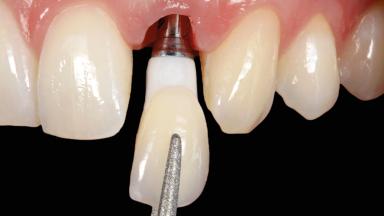

In this case, Arndt Happe describes how he achieved a stable outcome at 5 years by giving careful attention to the coronal aspect of the transmucosal area of the provisional, creating a slim emergence profile.

| Implant-supported provisional restoration | Required, elevated esthetic and/or functional demands |